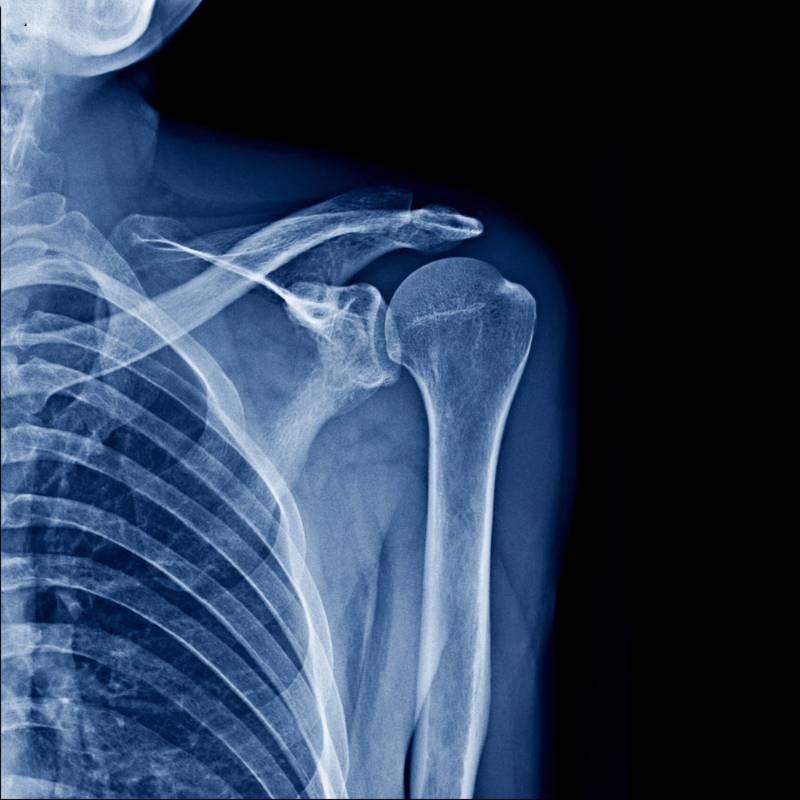

Sinar-X pada bahu untuk melihat kecederaan atau gangguan.